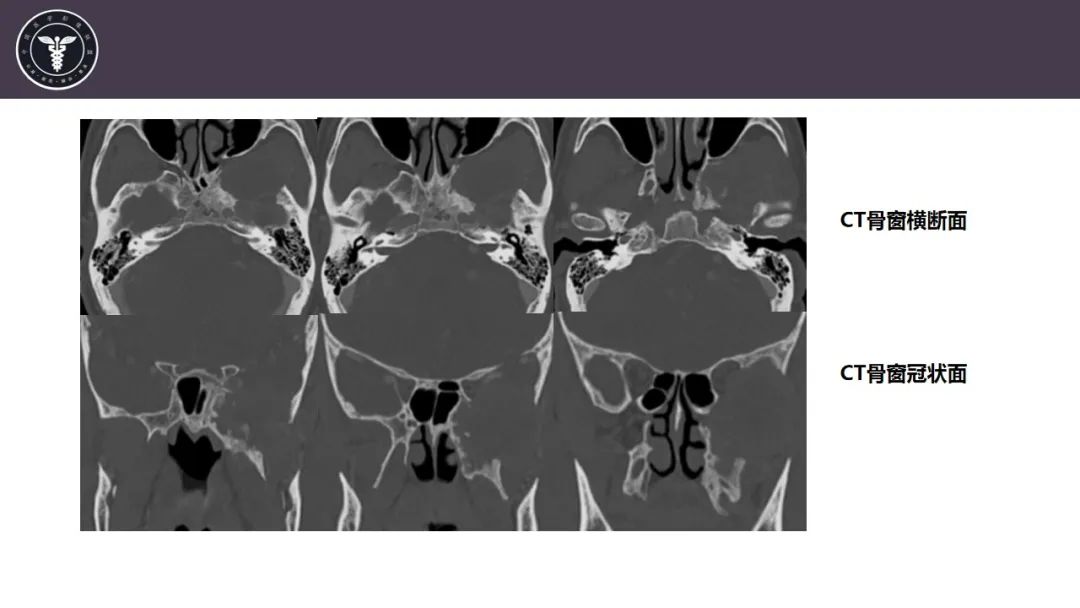

【病例】咬肌间隙肌纤维母细胞肉瘤1例MR诊断与鉴别-6

【病例】咬肌间隙肌纤维母细胞肉瘤1例MR诊断与鉴别-7